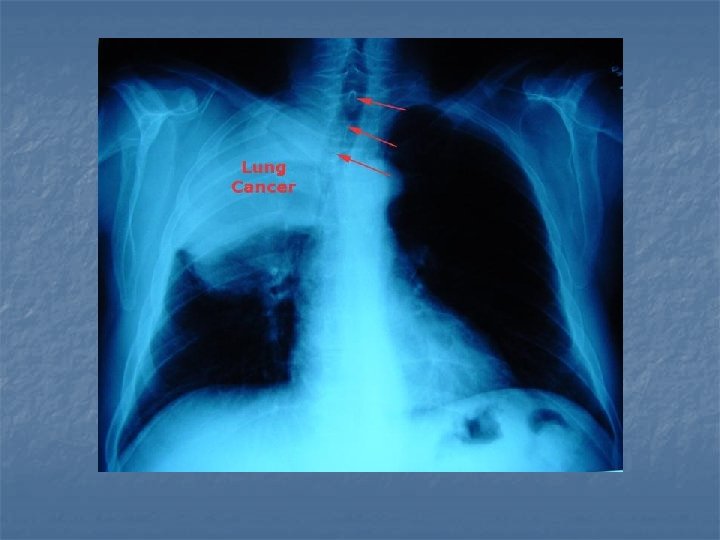

LUNG CANCER - diagnosis n n n X-ray CT scan (computed tomography – a cross-section of the lungs is taken) Helical low-dose CT scan detect very small tumours (see right)